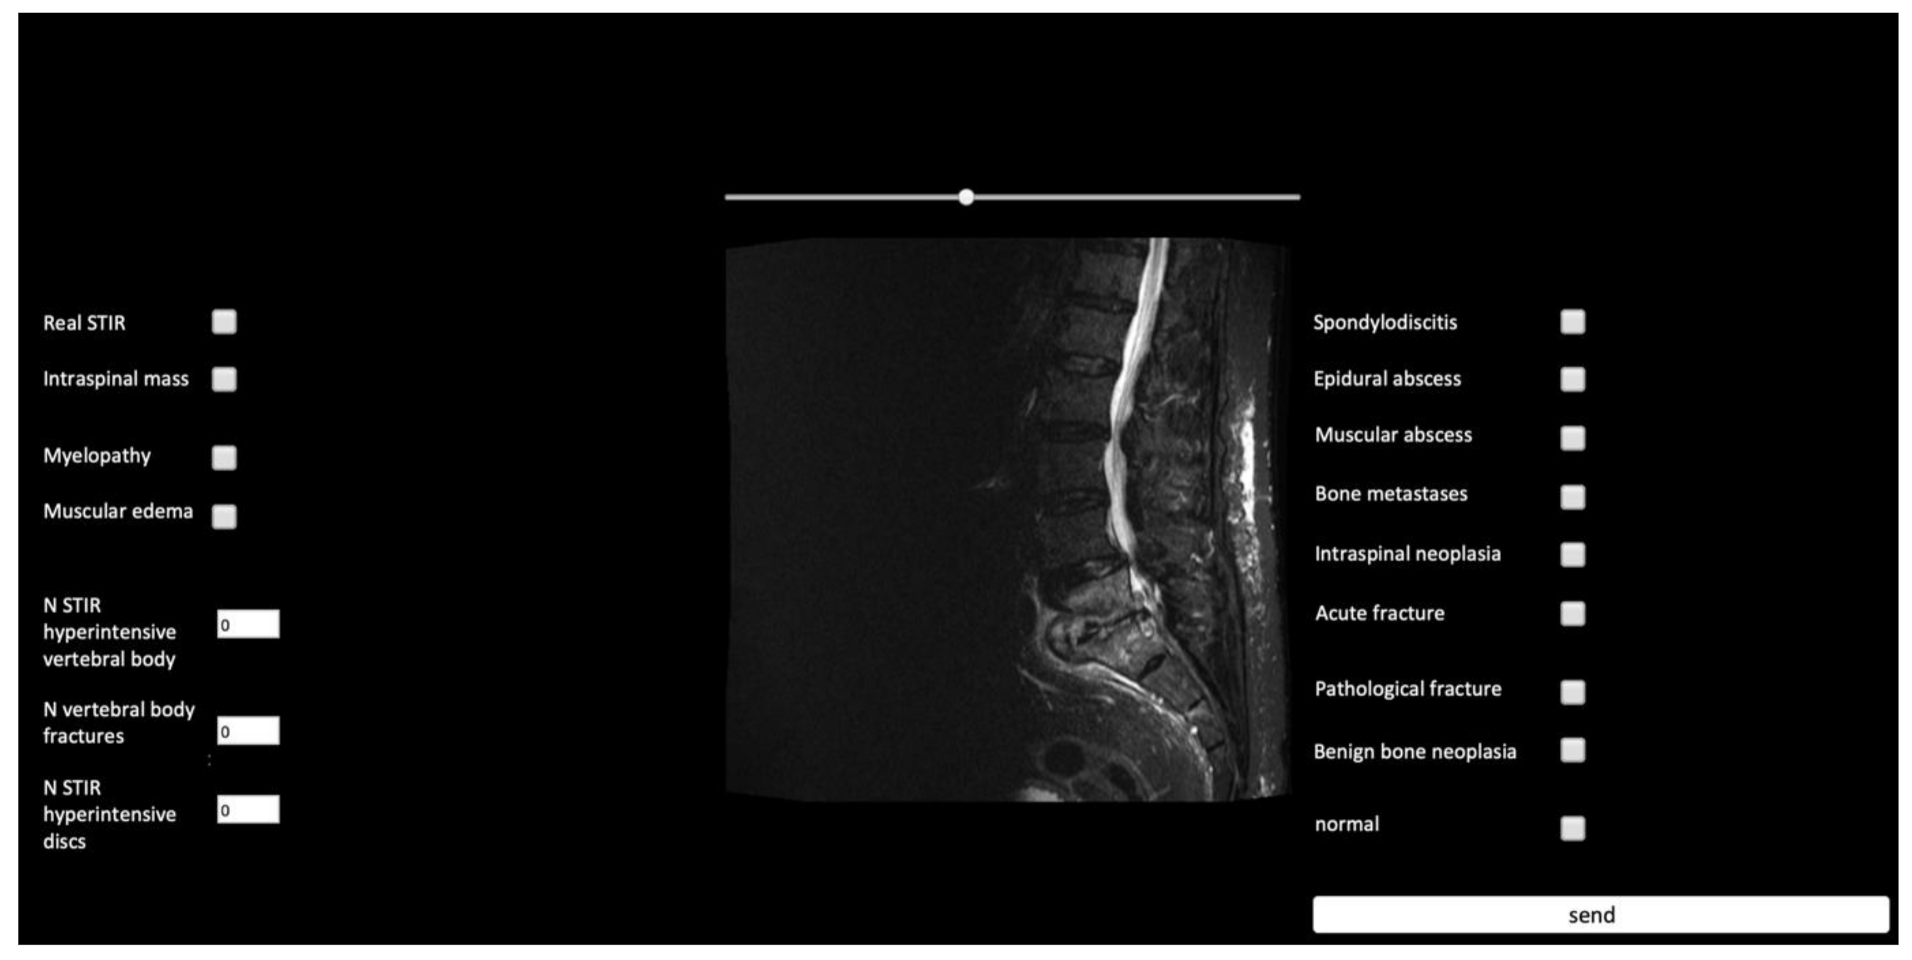

2.4. Validation